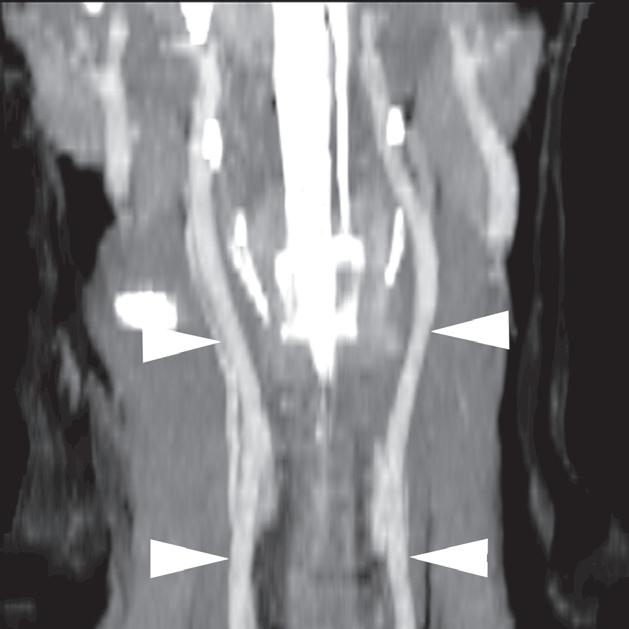

Badanie wykonano u 12-letniej, kastrowanej samicy labradora retrievera z wcześniej zdiagnozowanymi masami płucnymi i szyjnymi. W badaniu USG uwidoczniono kulisty, hipoechogeniczny guzek w obrębie prawego płata tarczycy (a). W TK masa jest nieznacznie hipodensyjna w obrazach bez wzmocnienia (b – strzałka). Lewy płat tarczycy ma prawidłową wielkość i jest hiperdensyjny (b – grot strzałki). Masa ulega umiarkowanemu wzmocnieniu po podaniu środka kontrastowego, jednak w mniejszym stopniu niż sąsiedni prawidłowy miąższ tarczycy (c – strzałka) i jej przeciwległy płat. W obrazach w rekonstrukcji grzbietowej w projekcji MIP po podaniu środka kontrastowego uwidoczniono przebieg obu tętnic szyjnych wspólnych dogrzbietowo względem płatów tarczycy (d – groty strzałek). Cieńszy przekrój MIP wykluczający tętnice szyjne ukazuje płaty tarczycy (e – strzałki) oraz lokalizację masy w obrębie prawego płata (e – grot strzałki). Biopsja wycinkowa wykazała raka tarczycy o utkaniu litym i pęcherzykowym z naciekaniem naczyń i torebki